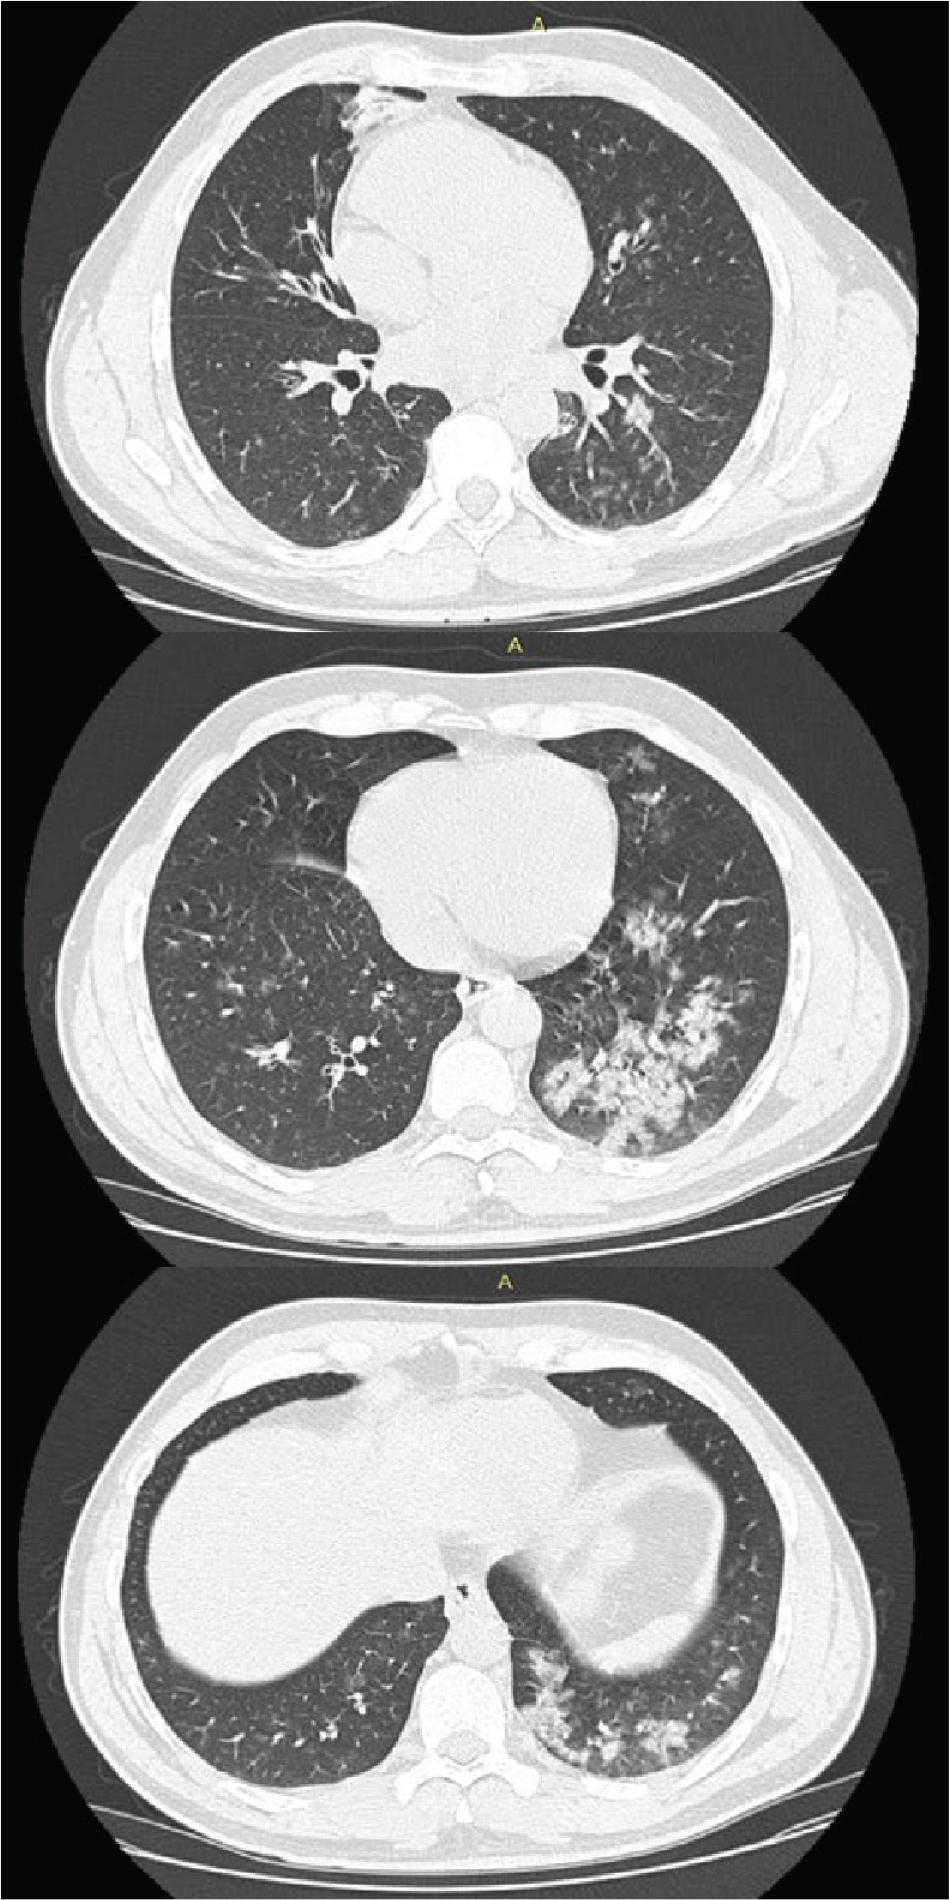

Chest computed tomography revealed pulmonary condensations, with a pseudonodular appearance, but also with a tendency to confluence in patches (at the posterobasal level on the left side), located inferiorly in the medial segment of the middle lobe and at the level of both lower lobes (left > right), in places associated with ground-glass opacities and perilesional interlobular septal thickening (Figure 1).

Computer tomography showing areas of pulmonary condensation with bilateral ground glass opacities.